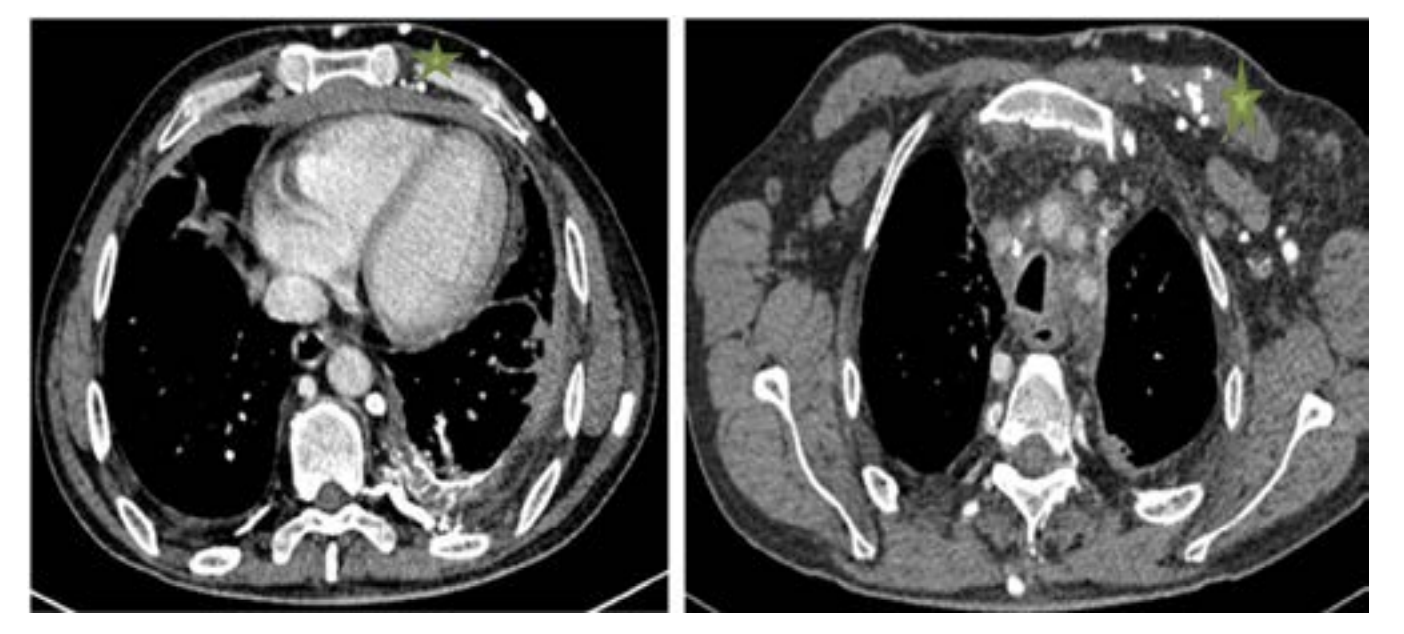

The diagnosis of SVCS is straightforward; it can be based on clinical findings. The chest CT scan is considered the main imaging tool to establish diagnosis, map, and evaluate the SVCS.5,6

The caval stenosis, in the series, was diagnosed by means of an angio CT scan of the chest, followed by confirmation using the venacavogram.

In what concerns the place of imaging exploration, the majority of authors believe that CT-scan with its high-quality multiplanar reconstructions is a crucial imaging tool. In fact, angio-CT scan confirms the diagnosis, determines the exact extent of obstruction, the nature and the degree of vena cava obstruction as well as it orients the placement of the endoprosthesis and the presence of associated pathologies.6 A venographic classification according to Stanford and Doty was set. Four Patterns of venous collateral return have been described.5 The 4th one matches with the most severe in terms of clinical symptoms (Schema 1).